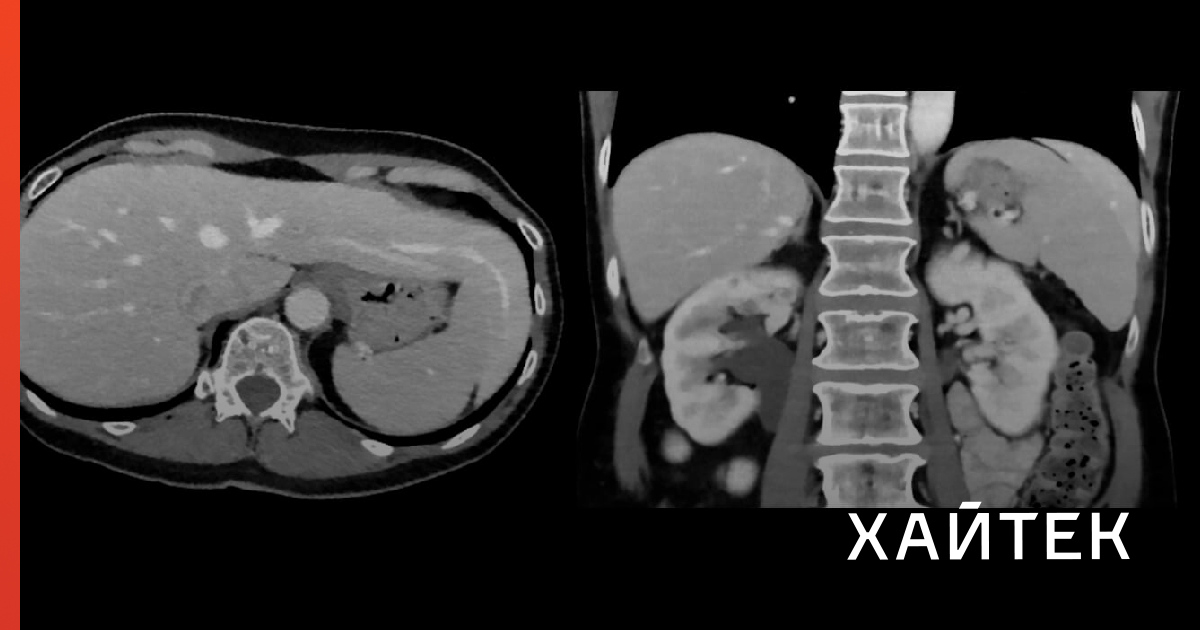

Печень может работать более 100 лет: ученые рассказали, как это возможно